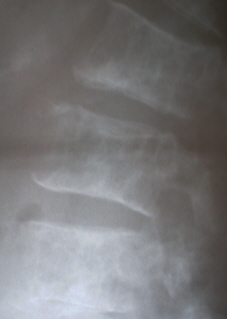

Иллюстрации 9, 10, 11. Множественные очаги деструкции костной ткани в поясничных позвонках и в крестце

Иллюстрации 12, 13, 14. Остеопоротическая трансформация костной ткани грудных позвонков с формированием патологического гиперкифоза, в результате клиновидной деформации тел позвонков и их уплощения (патологические переломы). Множественные очаги деструкции костной ткани округлой формы, без четких контуров.

Иллюстрации 15, 16. Аналогичные изменения в поясничных позвонках.